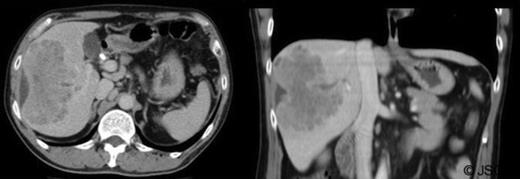

Abdominal ultrasound displayed biliary sludge although no gallstones with normal thin-walled gall-bladder. Abdominal CT-scan with contrast revealed a right liver mass involving segments V to VIII measuring 10.6cm×6cm axially and 10cm craniocaudally with mild caudate lobe hypertrophy suggesting underlying cirrhosis; intra-hepatic bile duct dilation, subcapsular fluid and lymphadenopathy (figure 1).